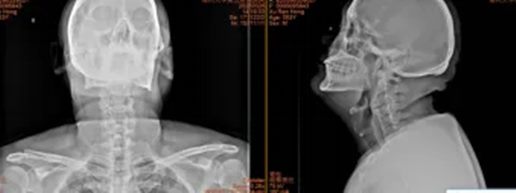

4.郑州市新密市米村镇赵女士60岁

术前:依托高分辨率CT、MRI及神经电生理监测,进行三维可视化手术规划

术中:在超声骨刀辅助下开展颈前路、颈后路或后路+前路等术式,并在神经电生理监护下确保减压彻底、置钉安全。